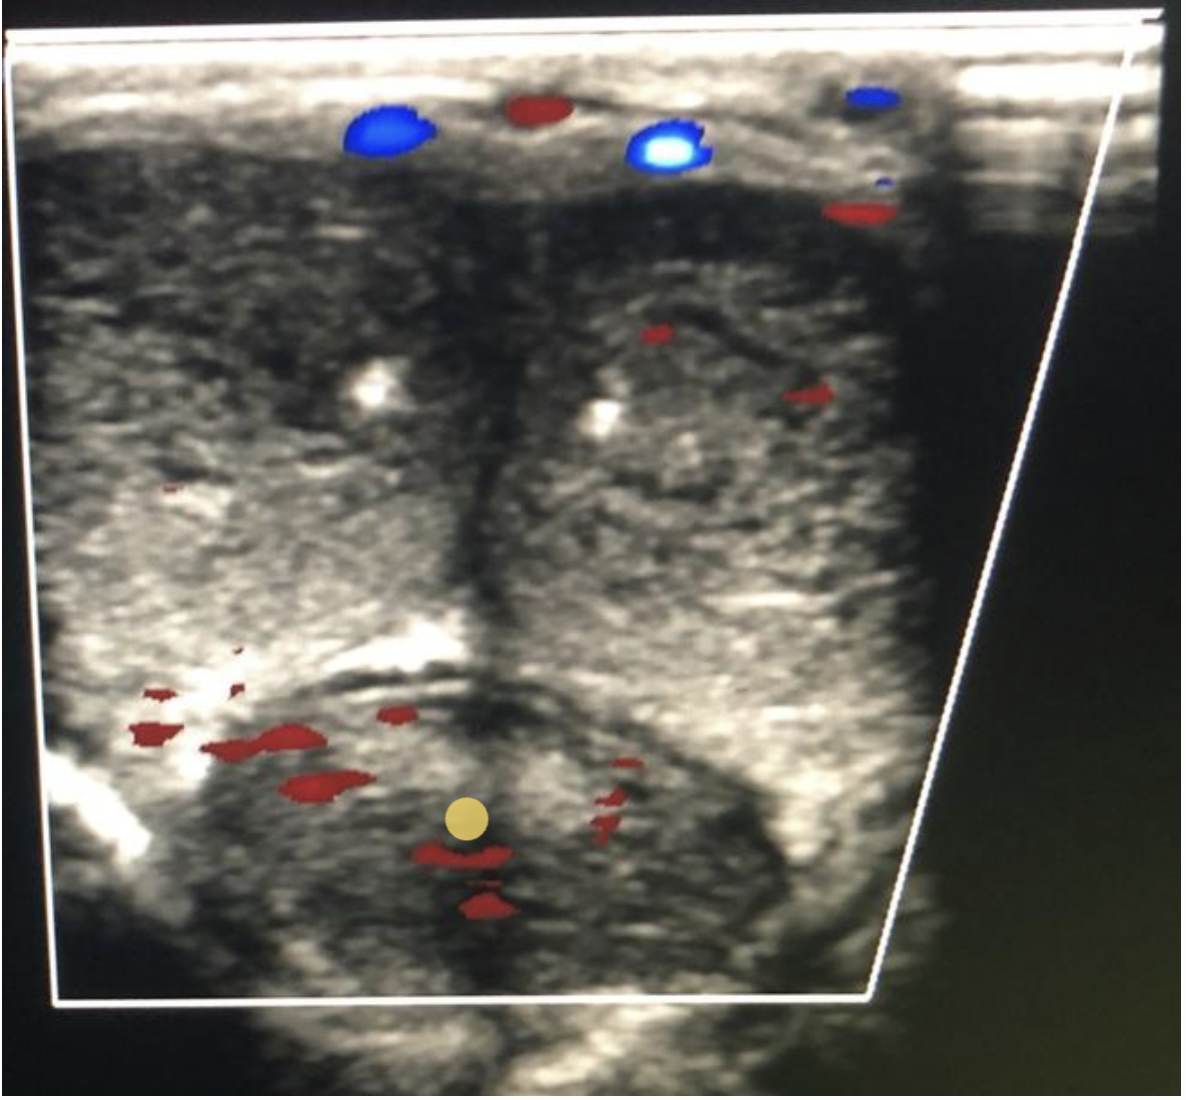

Which of the following is a characteristic of a normal lymph node?

C. thin hypochoic rim with hyperechoic central hilum

Normal lymph nodes are ovoid in shape. They do not demonstrate posterior enhancement. As lymph nodes enlarge with abnormal fluid accumulation, they appear more rounded and hypochoic/anechoic. The "plump" cortex causes decreased visualization of the central hilum. Color Doppler can be used to locate the hilum and main vascular supply. Posterior enhancement is present in structures posterior to abnormal nodes with significant fluid accumulation.

While scanning the thyroid, you identify a 0.6cm ovoid structure outside the thyroid, lateral to the left carotid artery. The structure has a thin hypoechoic rim surrounding a hyperechoic center. These findings are most suggestive of:

D. normal lymph node

Normal lymph nodes are ovoid in shape. They do not demonstrate posterior enhancement. As lymph nodes enlarge with abnormal fluid accumulation, they appear more rounded and hypoechoic/anechoic. The "plump" cortex causes decreased visualization of the central hilum. Color Doppler can be used to locate the hilum and main vascular supply. Posterior enhancement is present in structures posterior to abnormal nodes with significant fluid accumulation.

Find the normal lymph node

A normal lymph node is oval in shape and demonstrates a thin hypoechoic rim of tissue around an echogenic hilum. Abnormal lymph nodes demonstrate a more rounded shape, thickened cortex that can appear anechoic. and there is loss of differentiation of the hilum.